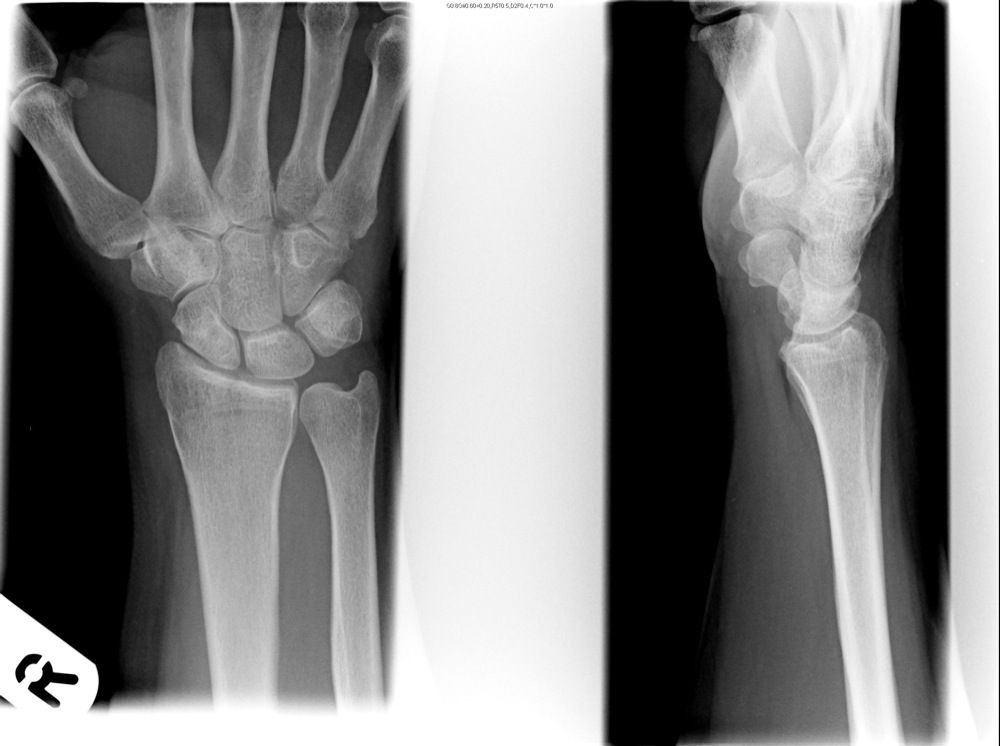

The carpal bone are sooo tiny. You have EIGHT whole bones in about a two finger width space at the base of your hand:

There are two “boats”, one carpel in the wrist and one tarsal at the ankle. Both bones were originally called navicular (L. = boat). But that apparently was confusing. “My patient broke her navicular bone.” “Well, which one??”. So they renamed the one in the wrist the scaphoid. (Gr = boat).